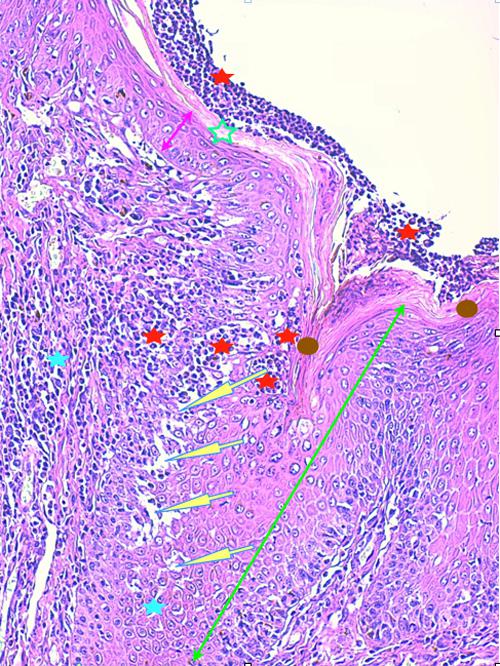

Photo 4 (Hémalun-Eosine X200) peau velue : Vue rapprochée de la Photo 3 montrant

la zone de fissuration de la gaine épithéliale externe d’un infundibula folliculaire avec lyse des

attaches desmosomiales intercellulaires et afflux de granulocytes éosinophiles donnant

naissance à des micro-pustules pariétales multiloculaires.

Légendes de la Photo 4 :

- Double flèche verte : grand axe de l’infundibulum folliculaire

- Double flèche rose : épiderme

- Flèches jaunes : fissuration de la gaine épithéliale externe avec lyse des attaches desmosomiales intercellulaires et afflux de granulocytes éosinophiles

- Ronds marrons : parakératose

- Étoiles rouges : micro-pustules pariétales multiloculaires (folliculite murale) et luminales obstruant l’abouchement folliculaire

- Étoiles turquoises : à gauche infiltrat inflammatoire dermique (au milieu en bas, erreur)

- Étoile vertes : orthokératose